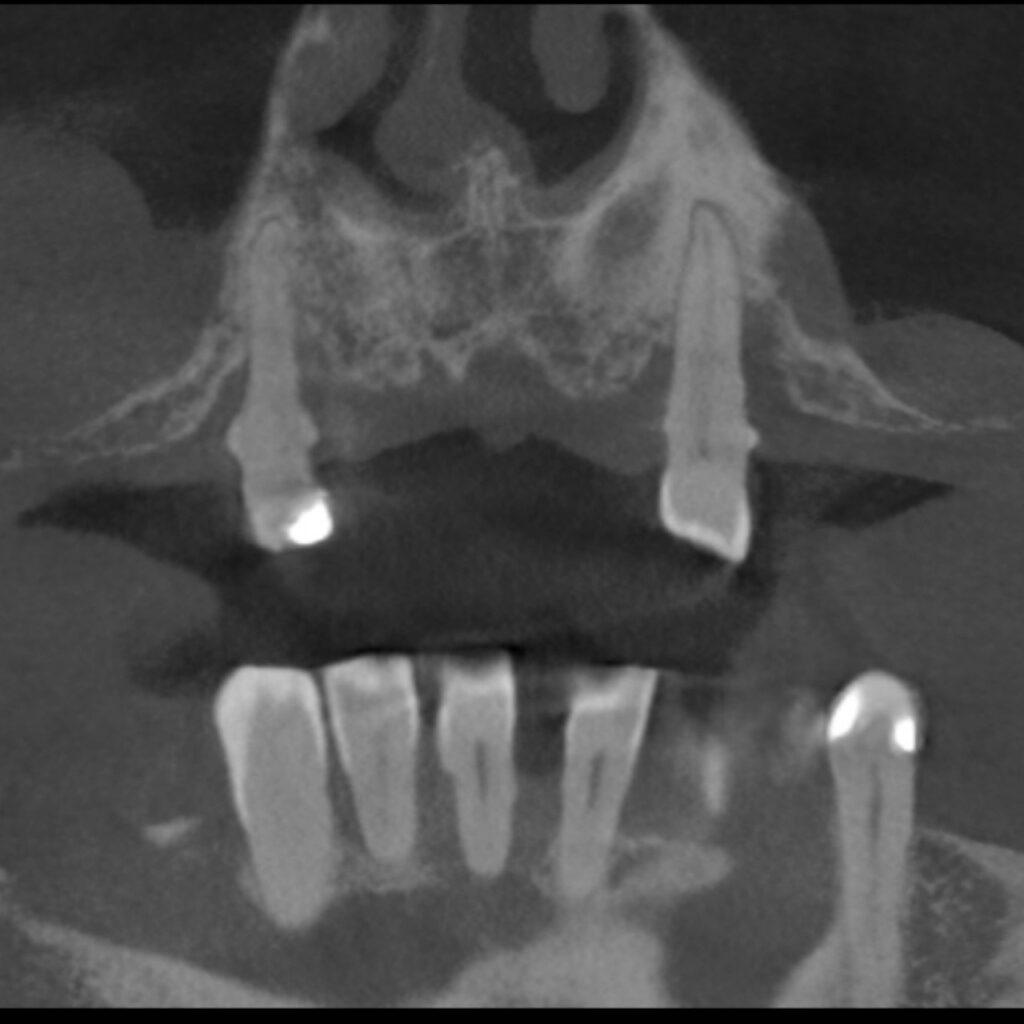

Robimy zdjęcie 3D, oceniamy stan kości i przedstawiamy opcje z cenami. Bez oceniania. Bez pospieszania.

Tak! Odbudowujemy kość specjalnymi zabiegami. Nawet jeżeli kości jest mało, mamy sprawdzone metody. SAFE ARCH jest zaprojektowany tak, by działać nawet przy znacznym zaniku kości. Przeczytaj więcej.

Im dłużej nosisz ruchomą protezę, tym bardziej zanika kość. Implant zatrzymuje ten proces.